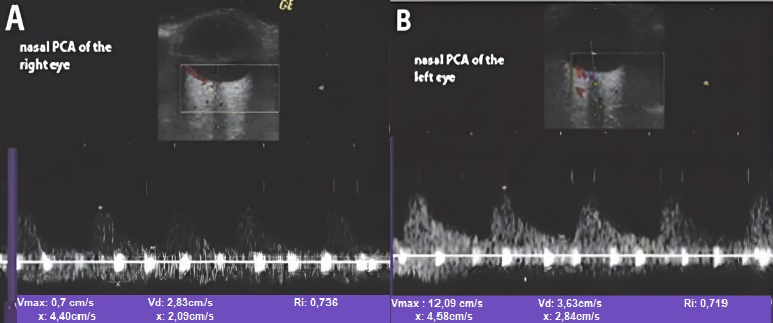

- Stenoses are characterized by aliasing and persistent diastolic flow by colour Doppler US. The peak systolic velocity (PSV) assessed within the stenosis area by pulsed-wave Doppler US is two or more times greater than the PSV recorded in the prestenotic segment of the vessel, with turbulence at the level of stenosis, associated with diminished velocities distal to the stenosis [30,31,32,33,34,35,36,37,38,39,40,41] (Figure 3) [11].